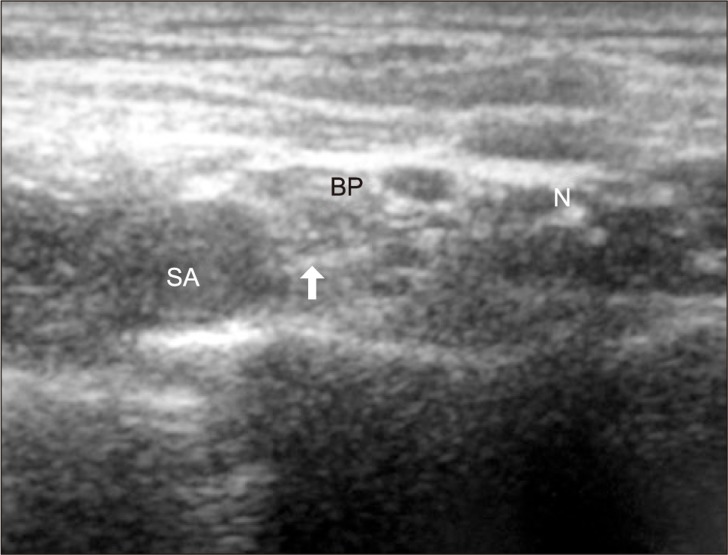

All blocks were performed by a single experienced operator and a single experienced assistant. An ultrasound machine (Vivid I®, GE Yokogawa Medical Systems Ltd., Tokyo, Japan) and a 12 MHz linear type probe were used. The supraclavicular fossa was scanned to locate the subclavian artery and brachial plexus cluster in a sterile fashion. A skin wheal was raised with 2 ml of 2% lidocaine. Using an in-plane technique, a 22 gauge, 5 cm, short beveled insulated needle (Stimuplex® D, B. Braun, Melsungen AG, Japan) was advanced from the lateral to medial. The needle was advanced and withdrawn repeatedly in zigzags to avoid nerve puncture until the needle tip was located near the lower trunk of brachial plexus during the approach (Fig. 1). Then it was confirmed that the location of the needle tip was not in hypoechoic nodules (in nerves) to avoid intraneural injection. For further safety, 0.5 ml of local anesthetic was injected as a test dose. If patients did not complain of paresthesia or pain, or injection pressure was not high, the remaining dose of local anesthetic was injected incrementally while withdrawing the needle.